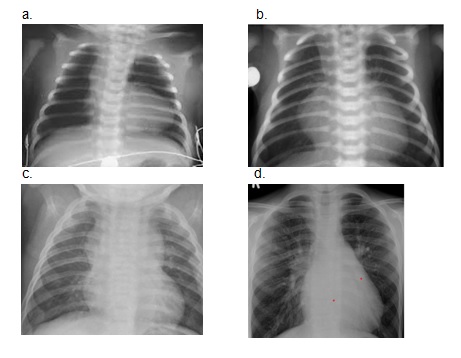

Dopasuj obrazy RTG do poszczególnych wad serca:

1) tetralogia Fallota;

2) ubytek przegrody międzyprzedsionkowej;

3) przełożenie wielkich pni tętniczych;

4) całkowity nieprawidłowy spływ żył płucnych.

Prawidłowe dopasowanie: